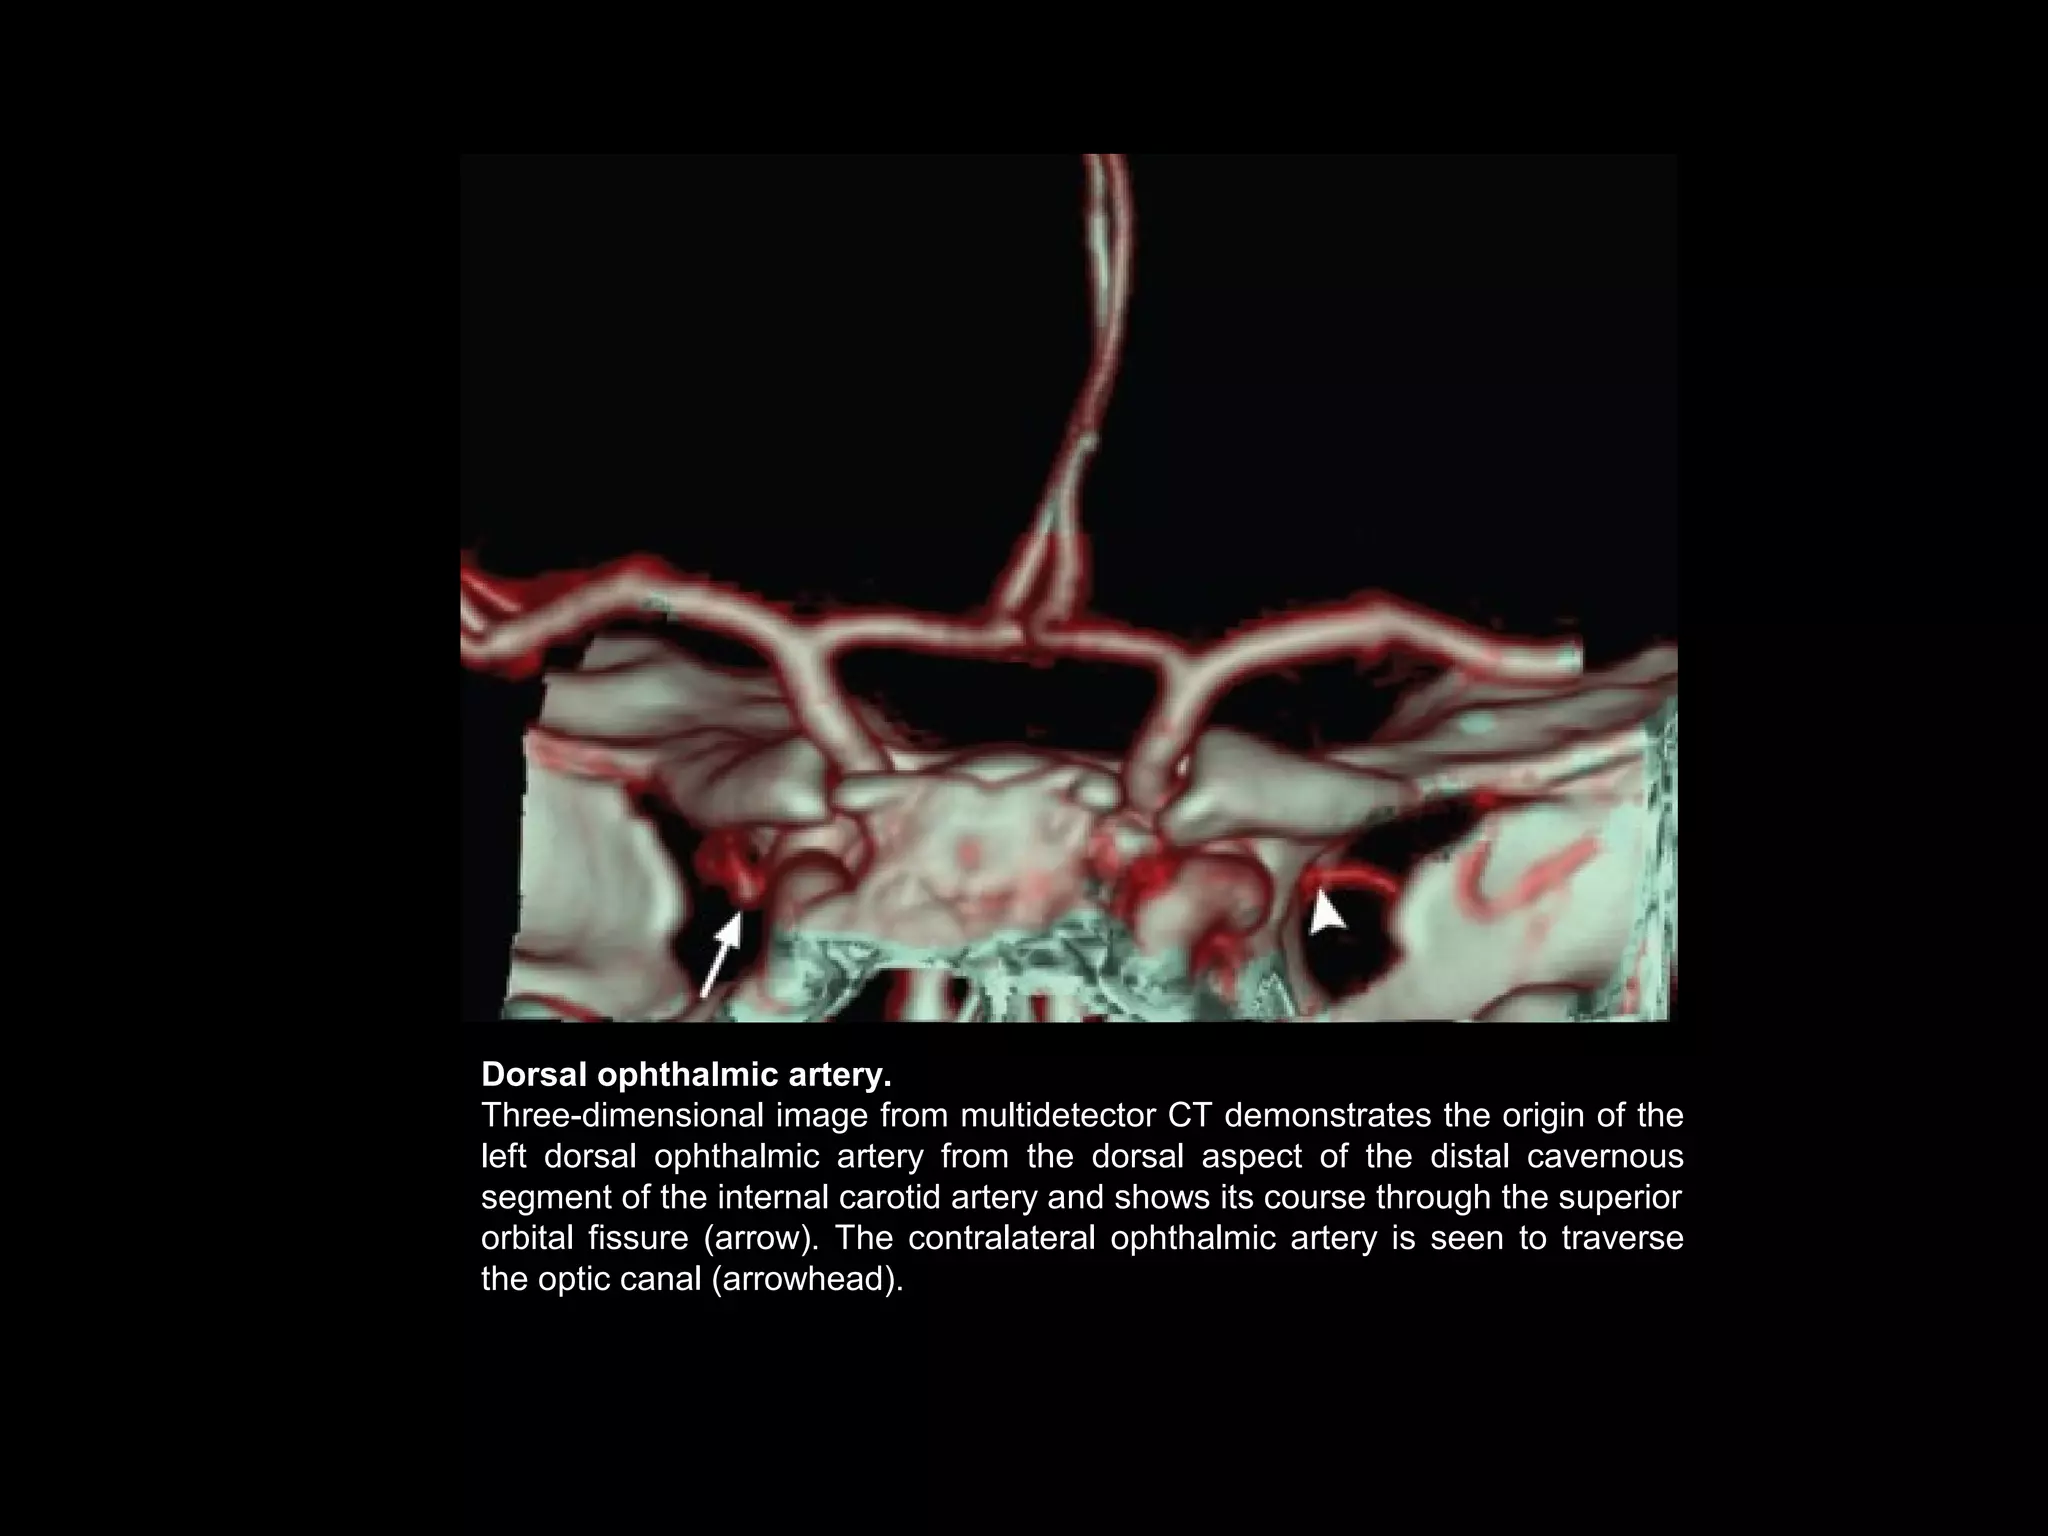

Persistent Dorsal Ophthalmic

• During early embryonic development, two

primitive ophthalmic arteries are present: The

and the dorsal ophthalmic artery persists.

• At CT, this anomalous artery is seen to arise

from the dorsal aspect of the supraclinoid

portion of the internal carotid artery and enter

the orbit by way of the superior orbital fissure

instead of the optic canal.

Dorsal ophthalmic artery.

Three-dimensional image from multidetector CT demonstrates the origin of the

left dorsal ophthalmic artery from the dorsal aspect of the distal cavernous

segment of the internal carotid artery and shows its course through the superior

orbital fissure (arrow). The contralateral ophthalmic artery is seen to traverse

the optic canal (arrowhead).